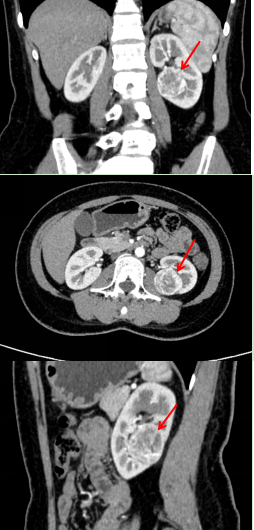

浦主任认真查看了李女士的CT图像:肿瘤大小约3.5*3.5*3.3cm,并不算大。然而肿瘤的位置较深,大部分埋于肾脏内,靠近肾盂和肾动脉,特别是肿瘤的上极紧贴两支肾动脉的分支。手术过程中一旦损伤动脉,很可能无法保留左肾,甚至可能引起大出血,危及生命。然而,直接进行左肾切除对于年轻的患者来说非常可惜。浦主任决定先将李女士收住入院,完善术前检查的同时组织科室内讨论,力争为患者制定安全可靠的保肾手术方案!

肿瘤上极毗邻肾动脉的两个分支

左肾肿瘤的冠状位、横断位、矢状位增强CT图像